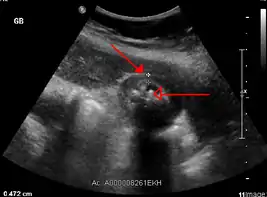

تتكون الحصوات الصفراوية عندما تَتَشبع العصارة الصفراوية، وغالبًا ما تكون إما مع الكولسترول أو البيليروبين.[6] مُعظم الحصوات الصفراوية لا تُسبب أعراضًا، حيثُ تبقى هذه الحصوات إما في المرارة أو تمر عبر الجهاز الصفراوي.[8] عندما تظهر الأعراض، فإنَّ ألمًا مغصيًا شديدًا عادةً ما يحدثُ في الجزء العلوي الأيمن من البطن.[6] قد يحدث التهابٌ في حال سدَّت الحصوة المرارة، أما إذا استقرت الحصوة في الجهاز الصفراوي، فإنهُ قد يحدث يرقان، وإذا سدت قناة البنكرياس فقد يحدث التهاب في البنكرياس.[8] تُشخص الحصوات الصفراوية باستخدام الموجات فوق الصوتية.[6] عند حدوث أعراض الحصوات الصفراوية، فإنه عادةً ما يتم التعامل معها بالانتظار حتى تمُر طبيعيًا،[8] ولكن نظرًا لاحتمال الإصابة المتكررة بالحصوات، فإنها غالبًا ما تُعالج بالإزالة الجراحية للمرارة،[8] ويُمكن أيضًا استعمال بعض الأدوية مثل حمض يوروديوكسي كوليك الذي يعمل على إذابة الحصوات. يمكن أيضًا استعمال تفتيت الحصيات، وهو عبارة عن إجراء يُستخدم لتفتيت الحصوات.[8]

عادةً ما يكون التصوير بالموجات فوق الصوتية أولَ فحصٍ تصويريٍ طبيٍ يُنفذُ مع أمراض المرارة مثل الشك بوجود حصواتٍ صفراوية.[8] من طُرق التصوير الأُخرى التصوير بالأشعة السينية للبطن أو التصوير المقطعي المحوسب، حيثُ قد تستخدم لفحص المرارة والأعضاء المحيطة بها.[8] يُمكن أيضًا استعمال خياراتٍ تصويرية أُخرى مثل تصوير البنكرياس والأوعية الصفراوية بالرنين المغناطيسي (MRCP) وتصوير البنكرياس والأقنية الصفراوية بالتنظير الباطني بالطريق الراجع (ERCP) وتصوير الأوعية الصفراوية بطريق الجلد أو أثناء العملية.[8] التصوير الومضاني الصفراوي هو تصويرٌ نووي يُستعمل لتقييم حالةِ المرارة.[45]